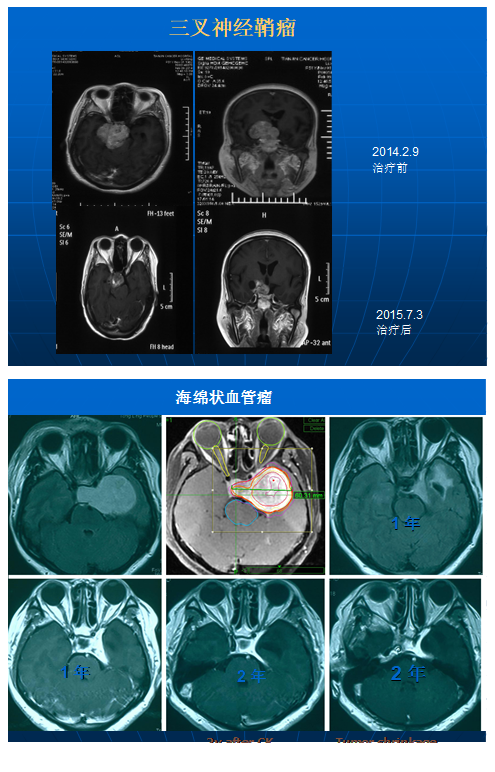

脑膜瘤、垂体瘤、听神经瘤、三叉神经鞘瘤、胶质瘤、脑转移瘤、AVM、三叉神经疼、脊髓肿瘤及脊柱肿瘤等。脑干肿瘤、颅底海绵状血管瘤、眼眶内、蝶窦、筛窦鼻腔的肿瘤及手术后残留、复发的肿瘤均可以。

“射波刀”虽不是传统意义上的刀,在一些肿瘤的治疗上以获的业界认可,可以作为首选治疗。常见的脑转移瘤、三叉神经鞘瘤、听神经瘤、海绵窦血管母细胞瘤、脑干肿瘤、血管畸形、三叉神经痛、脊柱肿瘤均可以首选治疗手段,这些疾病可以代替手术治疗。前提是要找到专业医生诊断明确,选择恰当。